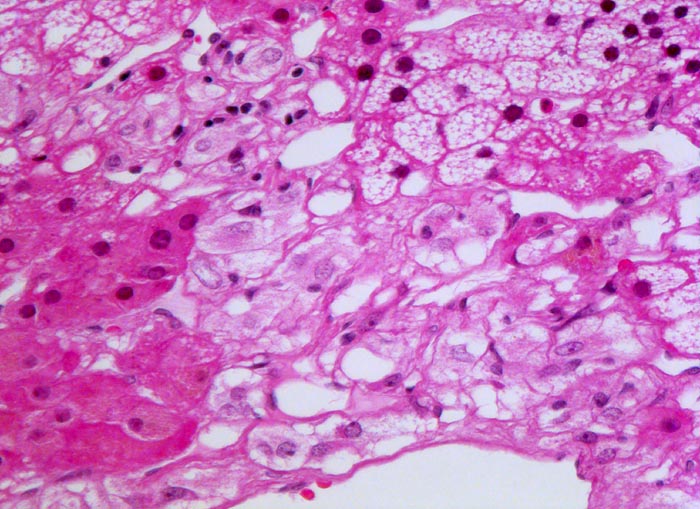

• Polygonale Tumorzellen mit reichlich granuliertem basophilem Zytoplasma und rundovalen Kernen mit uniform feinkörnigem Pfeffer und Salz Chromatin sowie prominentem Nukleolus.

• Herdförmig Tumorzellen mit sehr grossen polymorphen Zellkernen (links oben).